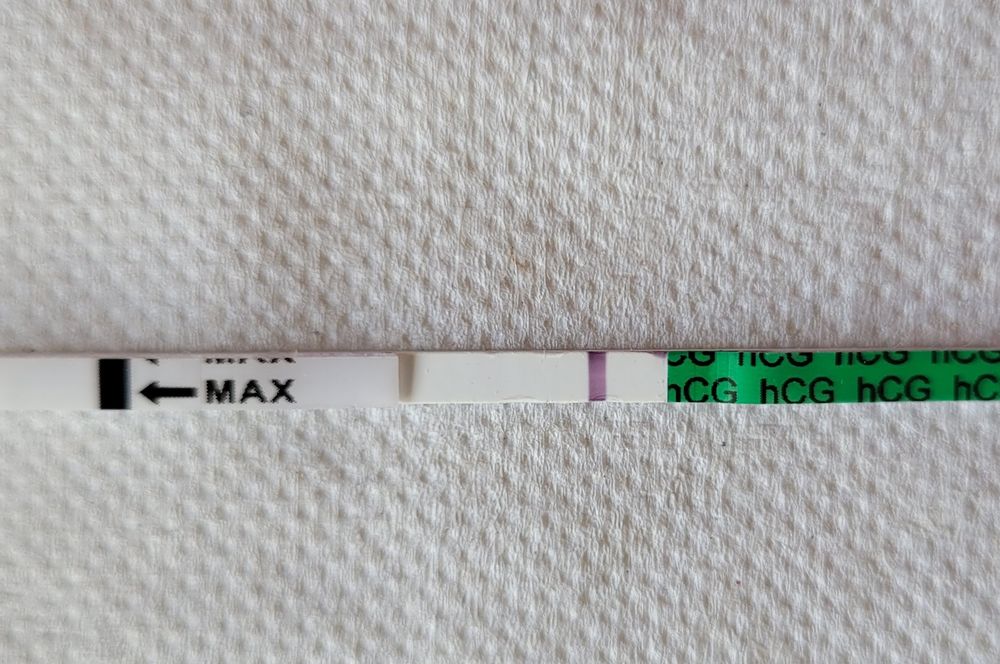

Пришла домой,начала готовить,открыла вино,налила,вспрмнила про тест. Пошла делать для отмаши. И тут увидела ее, невидимую розовую тень. Я знаю,многие не увидят ничего, а я за 2 года насмотрелась ,я знала,что вижу что-то.

Сразу нервы,слишком мало для шестидневки, бхб,замершая. Не радовалась. Вечером тест ,самый дорогой.

С 8 дпп начинаю делать тесты одной фирмы, тесты зебра, показывают,что и как хотят,тесты хорошие,поэтому не верьте тестам,верьте только хгч!